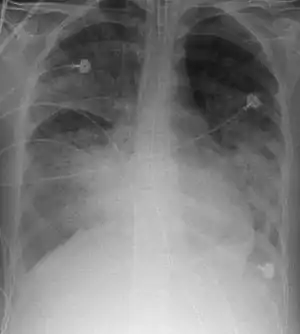

![]() Radiografie pulmonară în sindromul de detresă respiratorie acută | |

Aspectul radiologic (plămân alb, plămân dens) corespunde edemului interstițial și alveolar (plămân umed; atelectazie congestivă) ceea ce duce la diminuarea complianței pulmonare (plămân rigid). Sub un tablou clinic morfopatologic unitar, acest sindrom include leziuni pulmonare comparabile (edem, depozite fibrinoase, membrane hialine), dar de diferite cauze, din care bronhopatia cronică obstructivă sau insuficiența ventriculară stângă trebuie excluse. Diagnosticul se bazează pe asociație mai multor criterii: clinice: cianoză, tahipnee, tahicardie; radiografice: opacități bilaterale interstițiale și alveolare (edemul pulmonar necardiogen); biologice: presiunea arterială a oxigenului - PaO2 <50 mm Hg, poate coborî până la 30 mm Hg; funcționale: inhalarea O2 duce numai la o ușoară creștere a PaO2, poate exista o hipocapnie și uneori o acidoză asociată, presiunea capilară pulmonară este normală sau scăzută (<12 mm Hg) după deconectarea respiratorului. Capacitatea vitală este diminuată, precum și capacitatea funcțională reziduală, complianță este diminuată și buclele curbei presiune-volum sunt foarte perturbate. Schematic evoluția are loc în trei faze: (1) edem lezional cu leziunea pneumocitelor de tip I; (2) organizarea edemului interstițial (membrane hialine, infiltrația leucocitelor și fibroblastelor, obstrucția capilarelor cu fibrină și leucocite, proliferarea pneumocitelor de tip II); (3) dezvoltarea unei fibroze dezorganizate, deseori suprainfectate. Mortalitatea este ridicată (45% la adulții sub 65 de ani) devenind foarte mare în caz de insuficiență multiviscerală.[4][5][6][7][8]